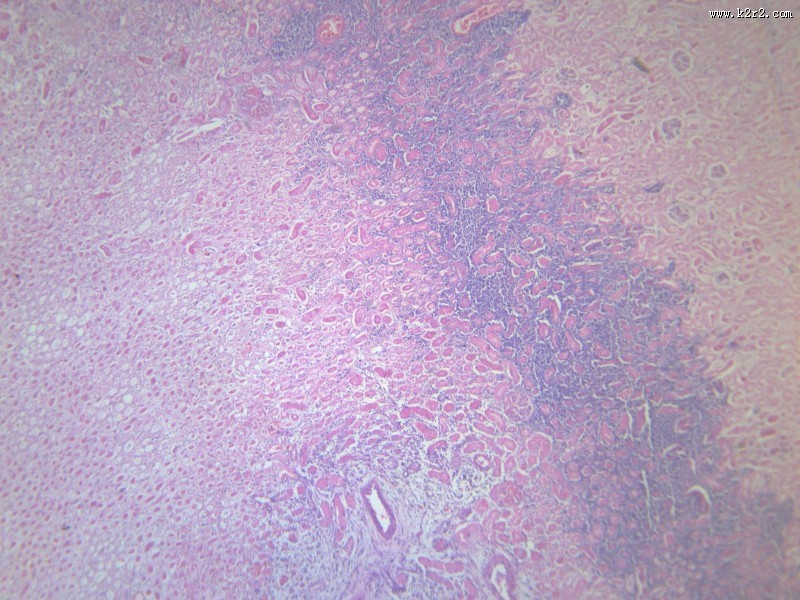

肾凝固性坏死 - 第1张

肾凝固性坏死

肾小管坏死

kidney coagulative necrosis